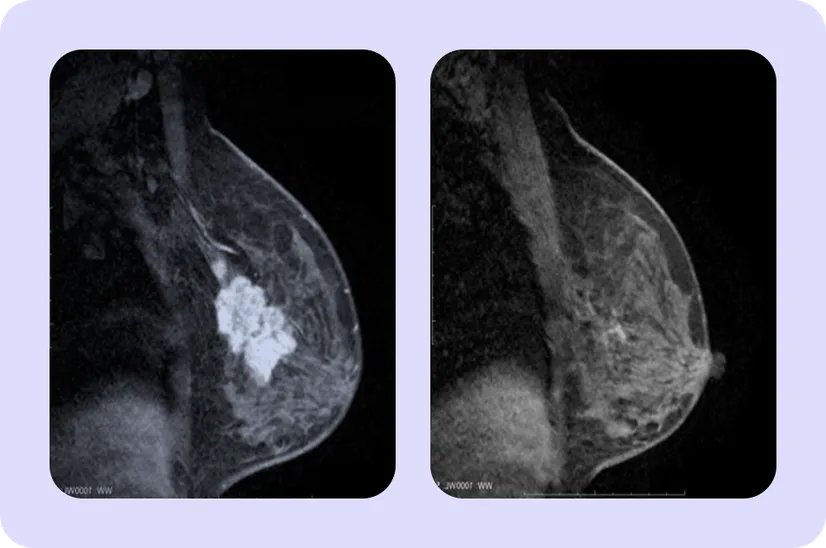

Об эффективности терапии говорит уменьшение размера опухоли. Для этого перед началом лечения врачи измеряют размеры новообразования, метастазов в лимфатических узлах с помощью маммографии или ультразвукового исследования (УЗИ). В некоторых случаях может использоваться магнитно-резонансная томография (МРТ). После завершения предоперационной терапии, исследования проводятся повторно, чтобы понять, как изменились размеры и распространенность опухоли9.

На первом изображении представлен пример полного ответа. Очаг уменьшился настолько, что перестал быть заметен на МРТ. Во втором случае наблюдается частичный ответ: очаг значительно уменьшился, но не исчез совсем10,11. МРТ лишь дополнительный метод исследования, ее проводят далеко не всем пациентам на неоадьювантной терапии, но в целях демонстрации эффекта мы выбрали именно этот метод.